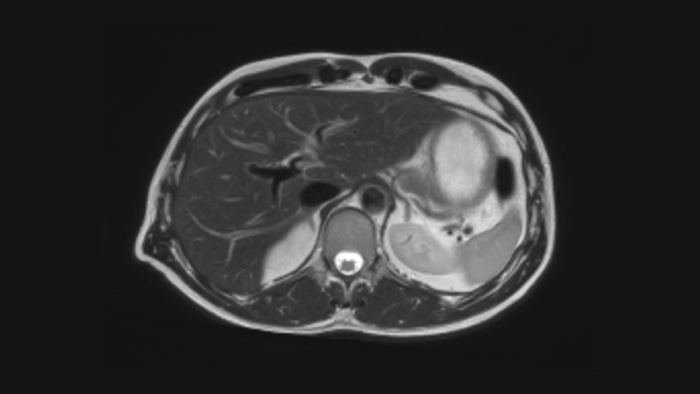

Medio cardíaco

Comodidad del paciente

Proporciona una reducción de hasta un 40% en las apneas, con una calidad de imagen prácticamente igual. 3